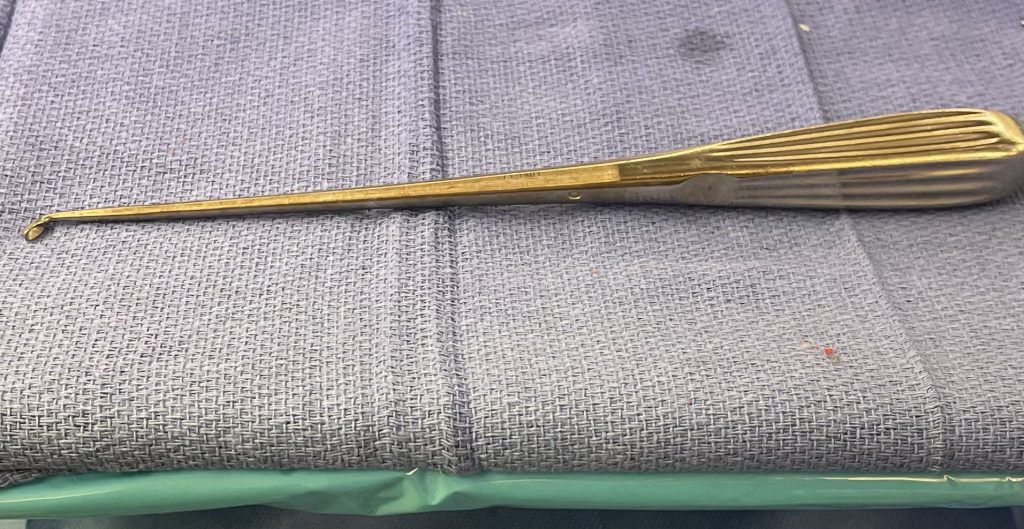

Fig 2: Kerrison device

Other maneuvers are always having a ready feeling of letting go of the tissue, having a light touch like “pumping your brakes”. Also, it is sometimes necessary to “shovel” the tissue, not bite it, with the Kerrison (Fig 2), utilizing the device as a dissecting instrument as well. It is also important to be patient and take the tissue in two bites, if necessary. It is ok to bite thickened tissue incompletely with the Kerrison if one is not sure if the consequence would be a leak or tear in the membrane if adhesions are present; dissect the adhesion with a Penfield 4 and cut it with a Metzenbaum scissors and then proceed with the finishing bite. The older patients are particularly challenging given the quality of their dura; it is often quite thin and floppy. A useful technique is employing an ultrasonic device (Fig 3) to remove enough of a shelf of bone to gain a dissection plane to allow for Kerrison to take over. And one can start with a 1 or 2 mm Kerrison to make a start under the edge of the bone and compressive soft tissue and advance to a 3 or 4mm.